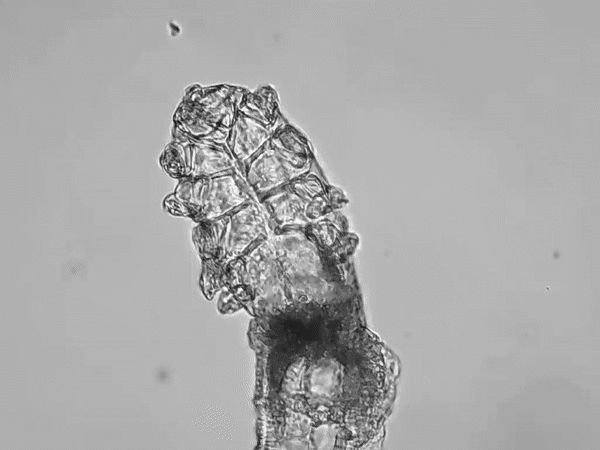

It can be caused by multiple factors including infestation of Demodex mites. Demodex mites are the most common ectoparasite found on humans. There are two species of Demodex – folliculorum and brevis – that live on the skin of the face and eyelids.

While they are highly prevalent in low numbers, it is an infestation of Demodex folliculorum mites that is implicated as a cause of blepharitis in 45% of cases.

Overcrowded mites scrape the epithelial cell lining with their claws and lay eggs in the follicle causing follicular distention, misdirected lashes, madarosis and irritation. Dead mites and collarettes also obstruct the hair follicle opening, leading to inflammation.